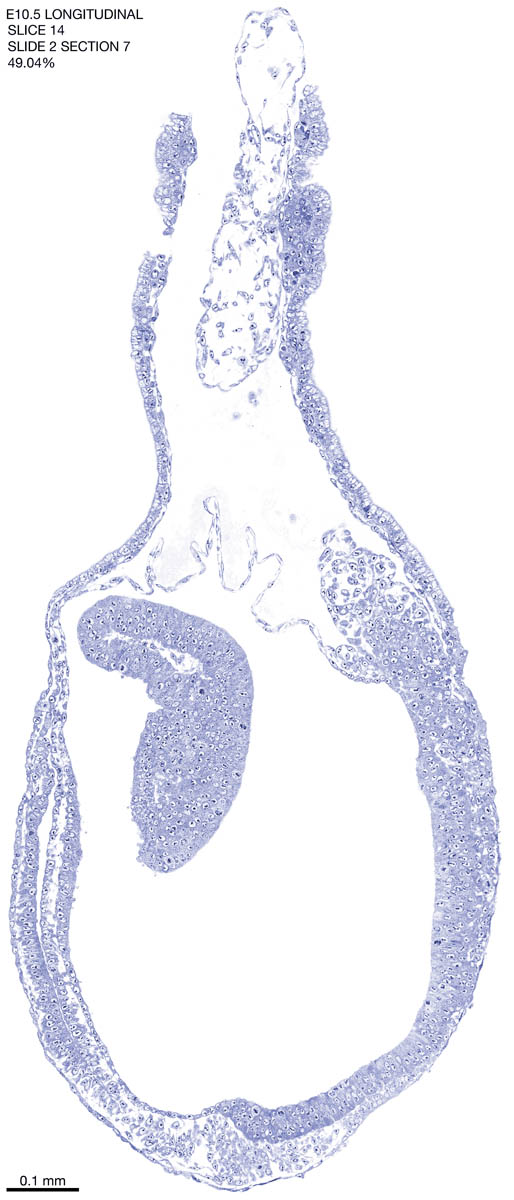

E10.5 Longitudianal Archive This page contains jpg files of ALL SLICES (each 3µm thick) that were scanned of the E10.5 longitudinally cut specimen. Download: Large | High Res Download: Large | High Res Download: Large | High Res Download: Large | High Res Download: Large | High Res Download: Large | High Res Download: Large | High Res Download: Large | High Res Download: Large | High Res Download: Large | High Res Download: Large | High Res Download: Large | High Res Download: Large | High Res Download: Large | High Res Download: Large | High Res Download: Large | High Res Download: Large | High Res Download: Large | High Res Download: Large | High Res Download: Large | High Res Download: Large | High Res Download: Large | High Res Download: Large | High Res Download: Large | High Res Download: Large | High Res Download: Large | High Res Download: Large | High Res Download: Large | High Res Download: Large | High Res Download: Large | High Res Download: Large | High Res Download: Large | High Res Download: Large | High Res Download: Large | High Res Download: Large | High Res Download: Large | High Res Download: Large | High Res Download: Large | High Res Download: Large | High Res Download: Large | High Res Download: Large | High Res Download: Large | High Res Download: Large | High Res Download: Large | High Res Download: Large | High Res Download: Large | High Res Download: Large | High Res Download: Large | High Res Download: Large | High Res Download: Large | High Res Download: Large | High Res Download: Large | High Res Download: Large | High Res Download: Large | High Res Download: Large | High Res Download: Large | High Res Download: Large | High Res Download: Large | High Res